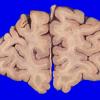

11B1 Pick Dz & ADNC (Case 11)_1

11B2 Pick Dz & ADNC (Case 11)_2

11B3 Pick Dz & ADNC (Case 11)_3

11B4 Pick Dz & ADNC (Case 11)_4

11B5 Pick Dz & ADNC (Case 11)_5

11B6 Pick Dz & ADNC (Case 11)_7

11B7 Pick Dz & ADNC (Case 11)_9

11B8 Pick Dz & ADNC (Case 11)_14